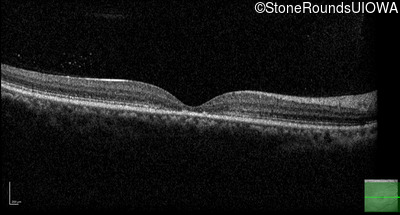

AR Stargardt Disease (IIA)

Age at visit:

15 years

OD

OS

20/125 -1

20/80

AR Stargardt Disease

ABCA4

Val256Val GTG>GTT

Gly1961Glu GGA>GAA

AR